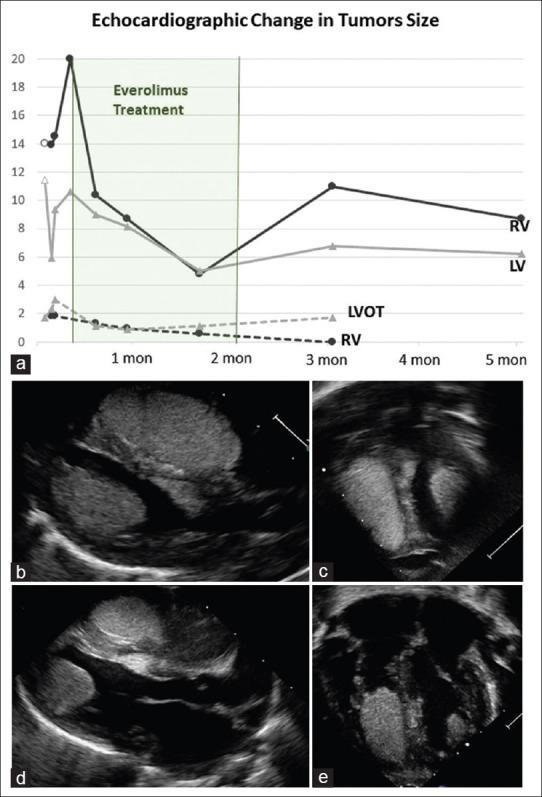

We report treating a term neonate with tuberous sclerosis and giant rhabdomyomas who presented with incessant supraventricular tachycardia with Everolimus. The treatment was efficient in reducing tumor size and assisted as an adjunct therapy in controlling arrhythmia and limiting preexcitation. Treatment was challenged by difficulty to achieve stable drug level and limited by neutropenia as a serious side effect.

我们报告了对一名患有结节性硬化症和巨大横纹肌瘤的足月儿使用依维莫司治疗,该患儿出现持续性室上性心动过速。该治疗在缩小肿瘤大小方面有效,并作为辅助治疗有助于控制心律失常和限制预激。治疗面临难以达到稳定药物水平的挑战,且受到严重副作用中性粒细胞减少的限制。